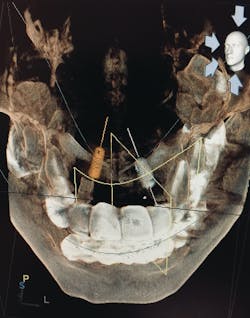

Digital imaging—whether traditional 2-D imaging with sensors, phosphor plates, or 3-D cone beam images— provides dental professionals and patients with diagnostic capabilities that previously were unimagined. Cone beam computed tomography (CBCT) has revolutionized dental imaging by bringing in the third dimension of imaging. Traditional 2-D imaging provides only height and width, while 3-D imaging provides the depth.3 Two-dimensional imaging is good for diagnosing simple concerns, while 3-D imaging lends itself to more in-depth diagnosis and use in complex treatment planning. Digital imaging combined with intraoral photography assists teams in increasing patient case acceptance. The old adage, “A picture is worth a thousand words,” is so true in today’s digitally enhanced practice. Patients understand and can take ownership of their health when they see the effects of disease. They can be involved in the results of care rather than just being told about it or viewing issues on small black-and-white images.